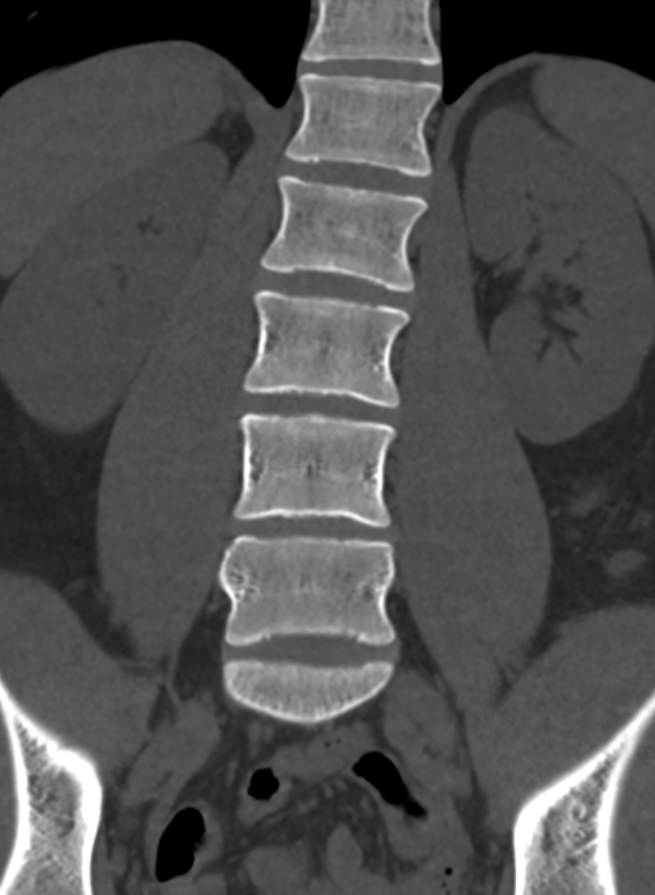

Мультиспиральная компьютерная томография является одним из наиболее информативных методов диагностики дегенеративно-дистрофических заболеваний, травматических, воспалительных изменений, а также опухолевых процессов позвоночника. Методика предусматривает использование рентгеновского излучения для получения детализированных снимков костных структур позвоночника, межпозвонковых суставов и межпозвоночных дисков.

В клинике «Доступная медицина» установлены современные мультиспиральные компьютерные томографы экспертного класса TOSHIBA AQUILION в различных модификациях (64-срезовый и 128-срезовый), на которых выполняются комплексные обследования позвоночника, включая одномоментное исследование несколько отделов. Аппараты производят сканирование с помощью рентгеновских лучей, делая тончайшие срезы с шагом от 0,5 мм, затем с помощью компьютерных программ полученные данные преобразуются в изображения трехмерного формата, что обеспечивает точность и достоверность диагностики.

С помощью мультиспиральной КТ можно диагностировать:

- патологические изгибы позвоночника, сколиоз, усиленный или выпрямленный лордоз как нарушение статической функции позвоночника;

- аномалии строения позвоночника.